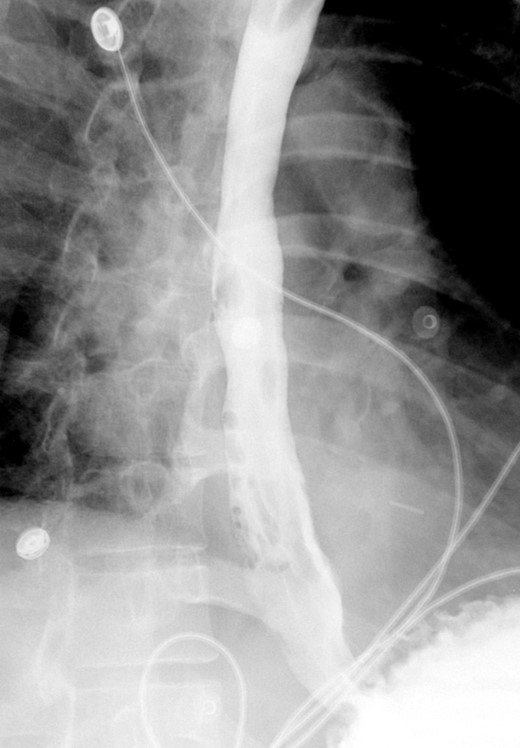

A computed tomographic scan revealed air and fluid surrounding the esophagus (Fig. 1). Esophagogram performed with water-soluble contrast media showed a distal esophageal perforation with a free leak into a large mediastinal cavity to the left of the esophagus (Fig. 2). The patient was triaged directly to the operation room. A left chest tube was placed with improvement in his oxygenation, and grossly murky fluid was drained. Esophagogastroduodenoscopy (EGD) was performed next and revealed a very small caliber esophagus with concentric ringed appearance. A tight stricture was noted in the mid-esophagus, which only allowed passage of a pediatric gastroscope. In the lower esophagus, a 2-cm tear with necrotic edges was visualized 3 cm above the gastroesophageal (GE) junction. With this diffusely strictured and very diseased appearance of the esophagus, the decision was made to proceed with stent placement and thoracoscopic drainage of the mediastinum rather than primary surgical repair via thoracotomy. A fully covered, 15 cm × 19 mm, EndoMAXX® esophageal stent was successfully placed covering the perforation site. Mediastinal washout and drainage was performed subsequently via left thoracoscopy. A postoperative esophagram showed no leak and the patient was started on a liquid diet that was tolerated well. His hospital stay was uneventful, and he was discharged on twice daily high-dose proton pump inhibitor (PPI) on post-operative Day 5. He was placed on a mechanical soft diet on discharge. Repeat upper GI study with water soluble contrast postoperatively showed no evidence extravasation. (Fig. 3)

Shows evidence of esophageal rupture and leak with pneumomediastinum and air and fluid surrounding the esophagus.